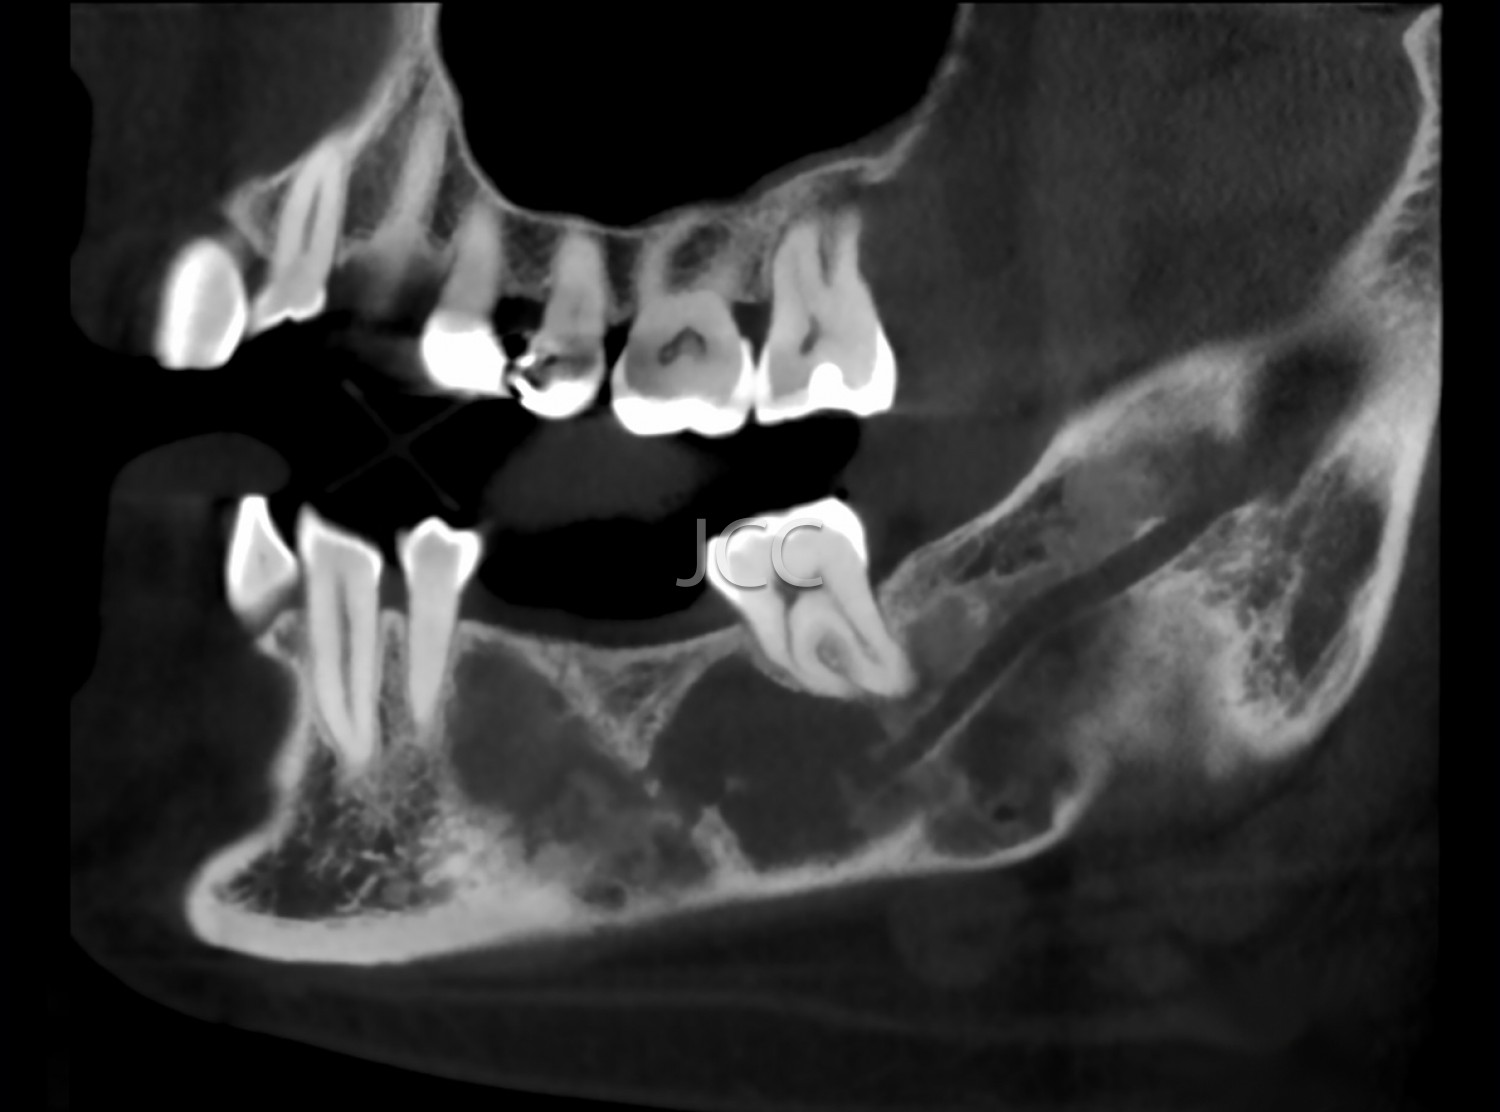

Dental Radiology - Maxillofacial CBCT / CT

Applications

• Orthognathic surgery

• Maxillofacial Surgery and Traumatology